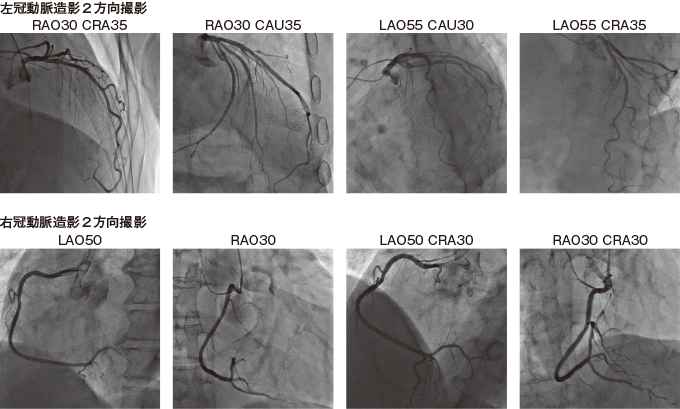

10冠動脈造影を行う(ニトロール®は医師からの指示があれば清潔操作で渡す。冠注するときは医師が声をかける)(写真7)。

写真7冠動脈造影画像

11病変部位を確認できたらPCIへ移行する。